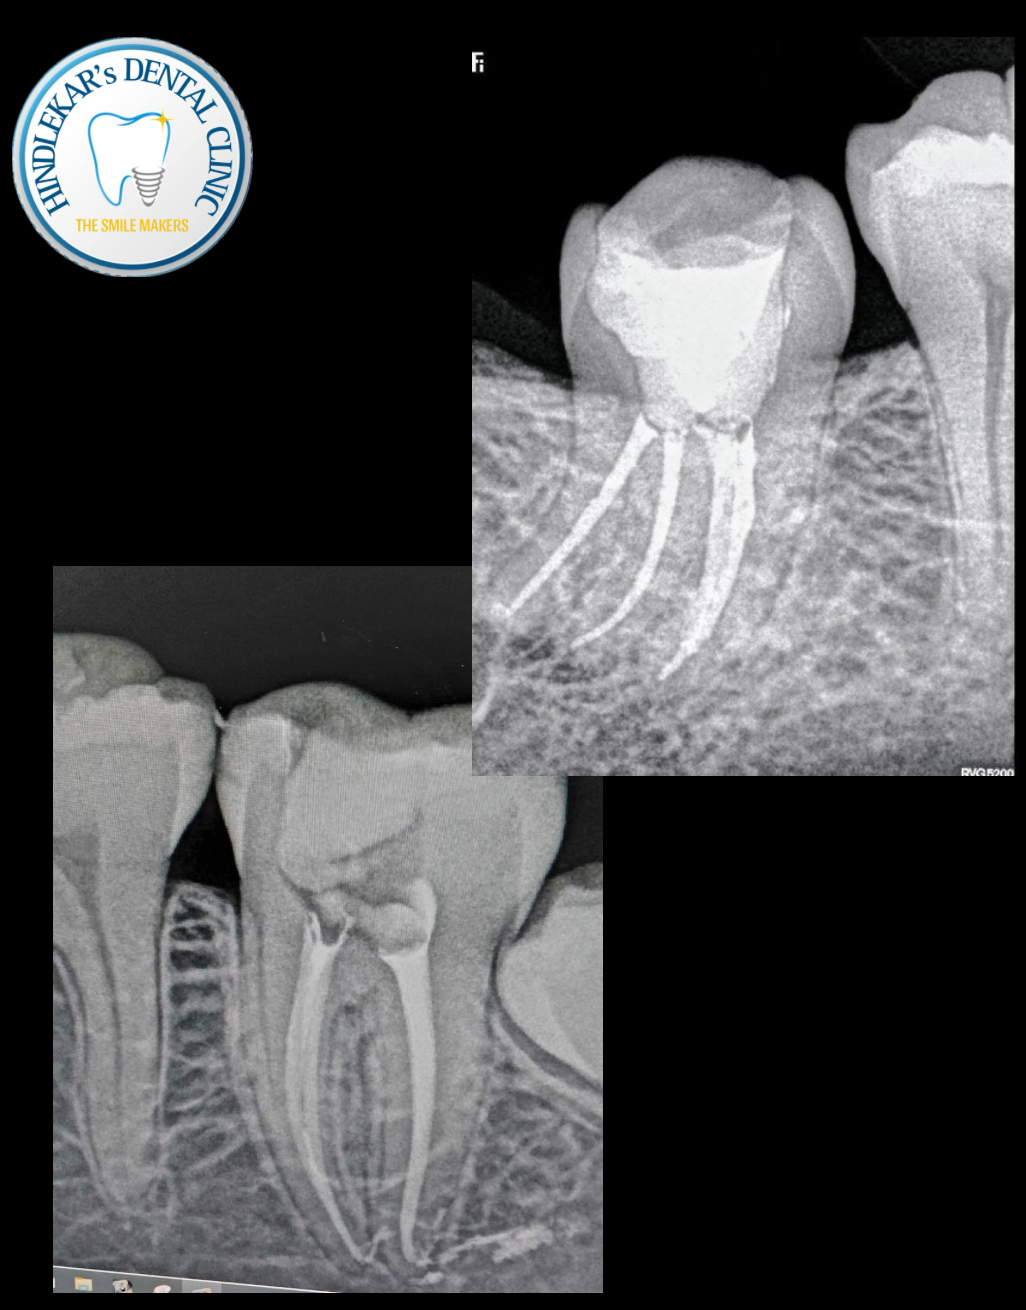

Save your natural tooth with Painless Root Canal Treatment by an experienced Root Canal Specialist. ✔ Single-visit treatment available ✔ Advanced technology ✔ Comfortable & pain-free procedure 🌐 www.drajithindlekar.com Book your consultation today at Dr Ajit Hindlekar’s dental clinic..